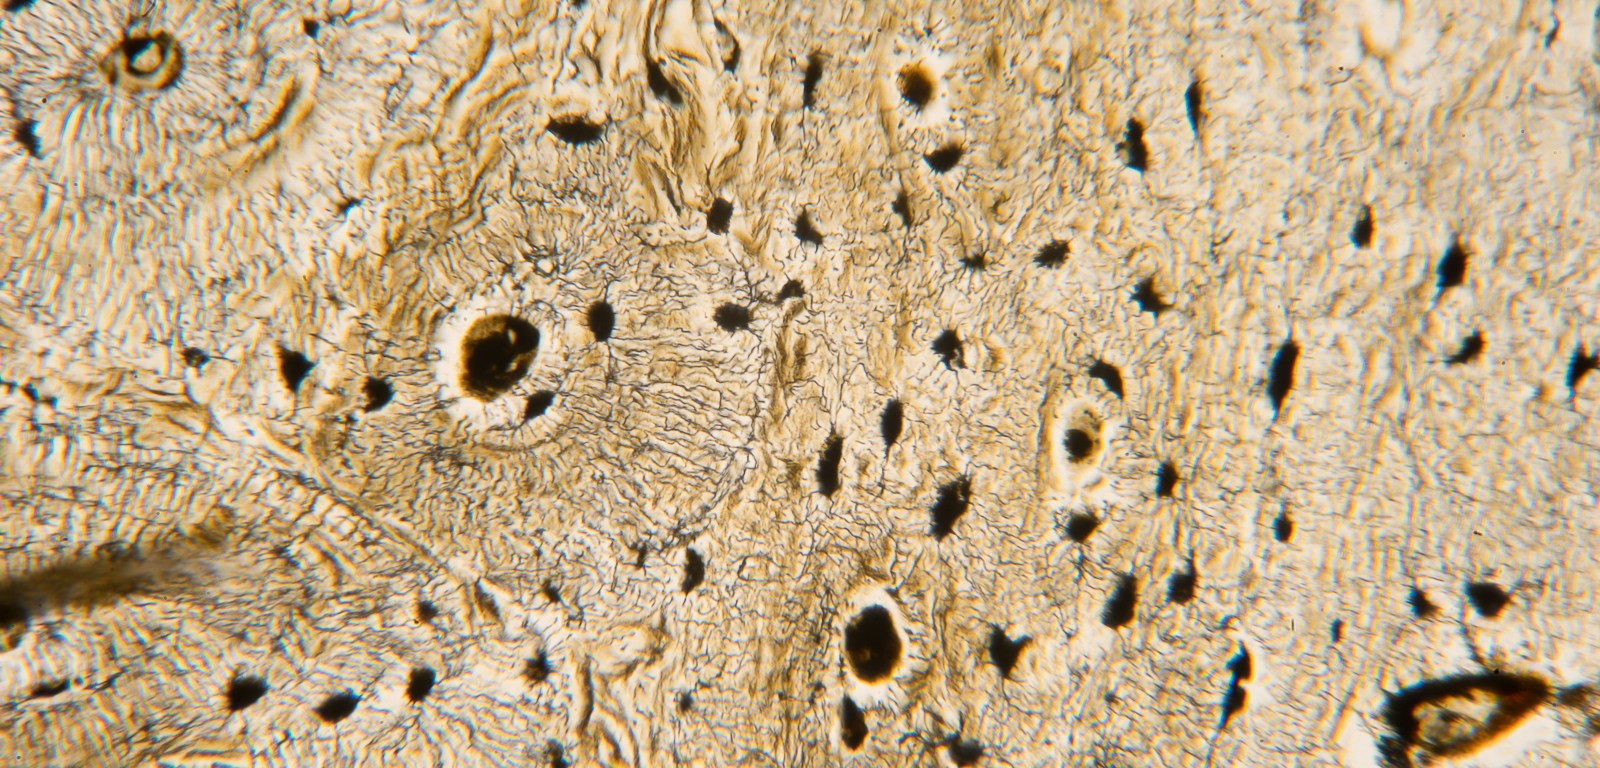

Compact bone (TM: 100x, picture taken with a Nikon Plan Apo 10/0.4 on Sony A7ii)

20170305_untitled_DSC7396

Compact bone.  (TM: 400x, picture taken with a Zeiss Planapo 40/1.0 Oil on Leica)